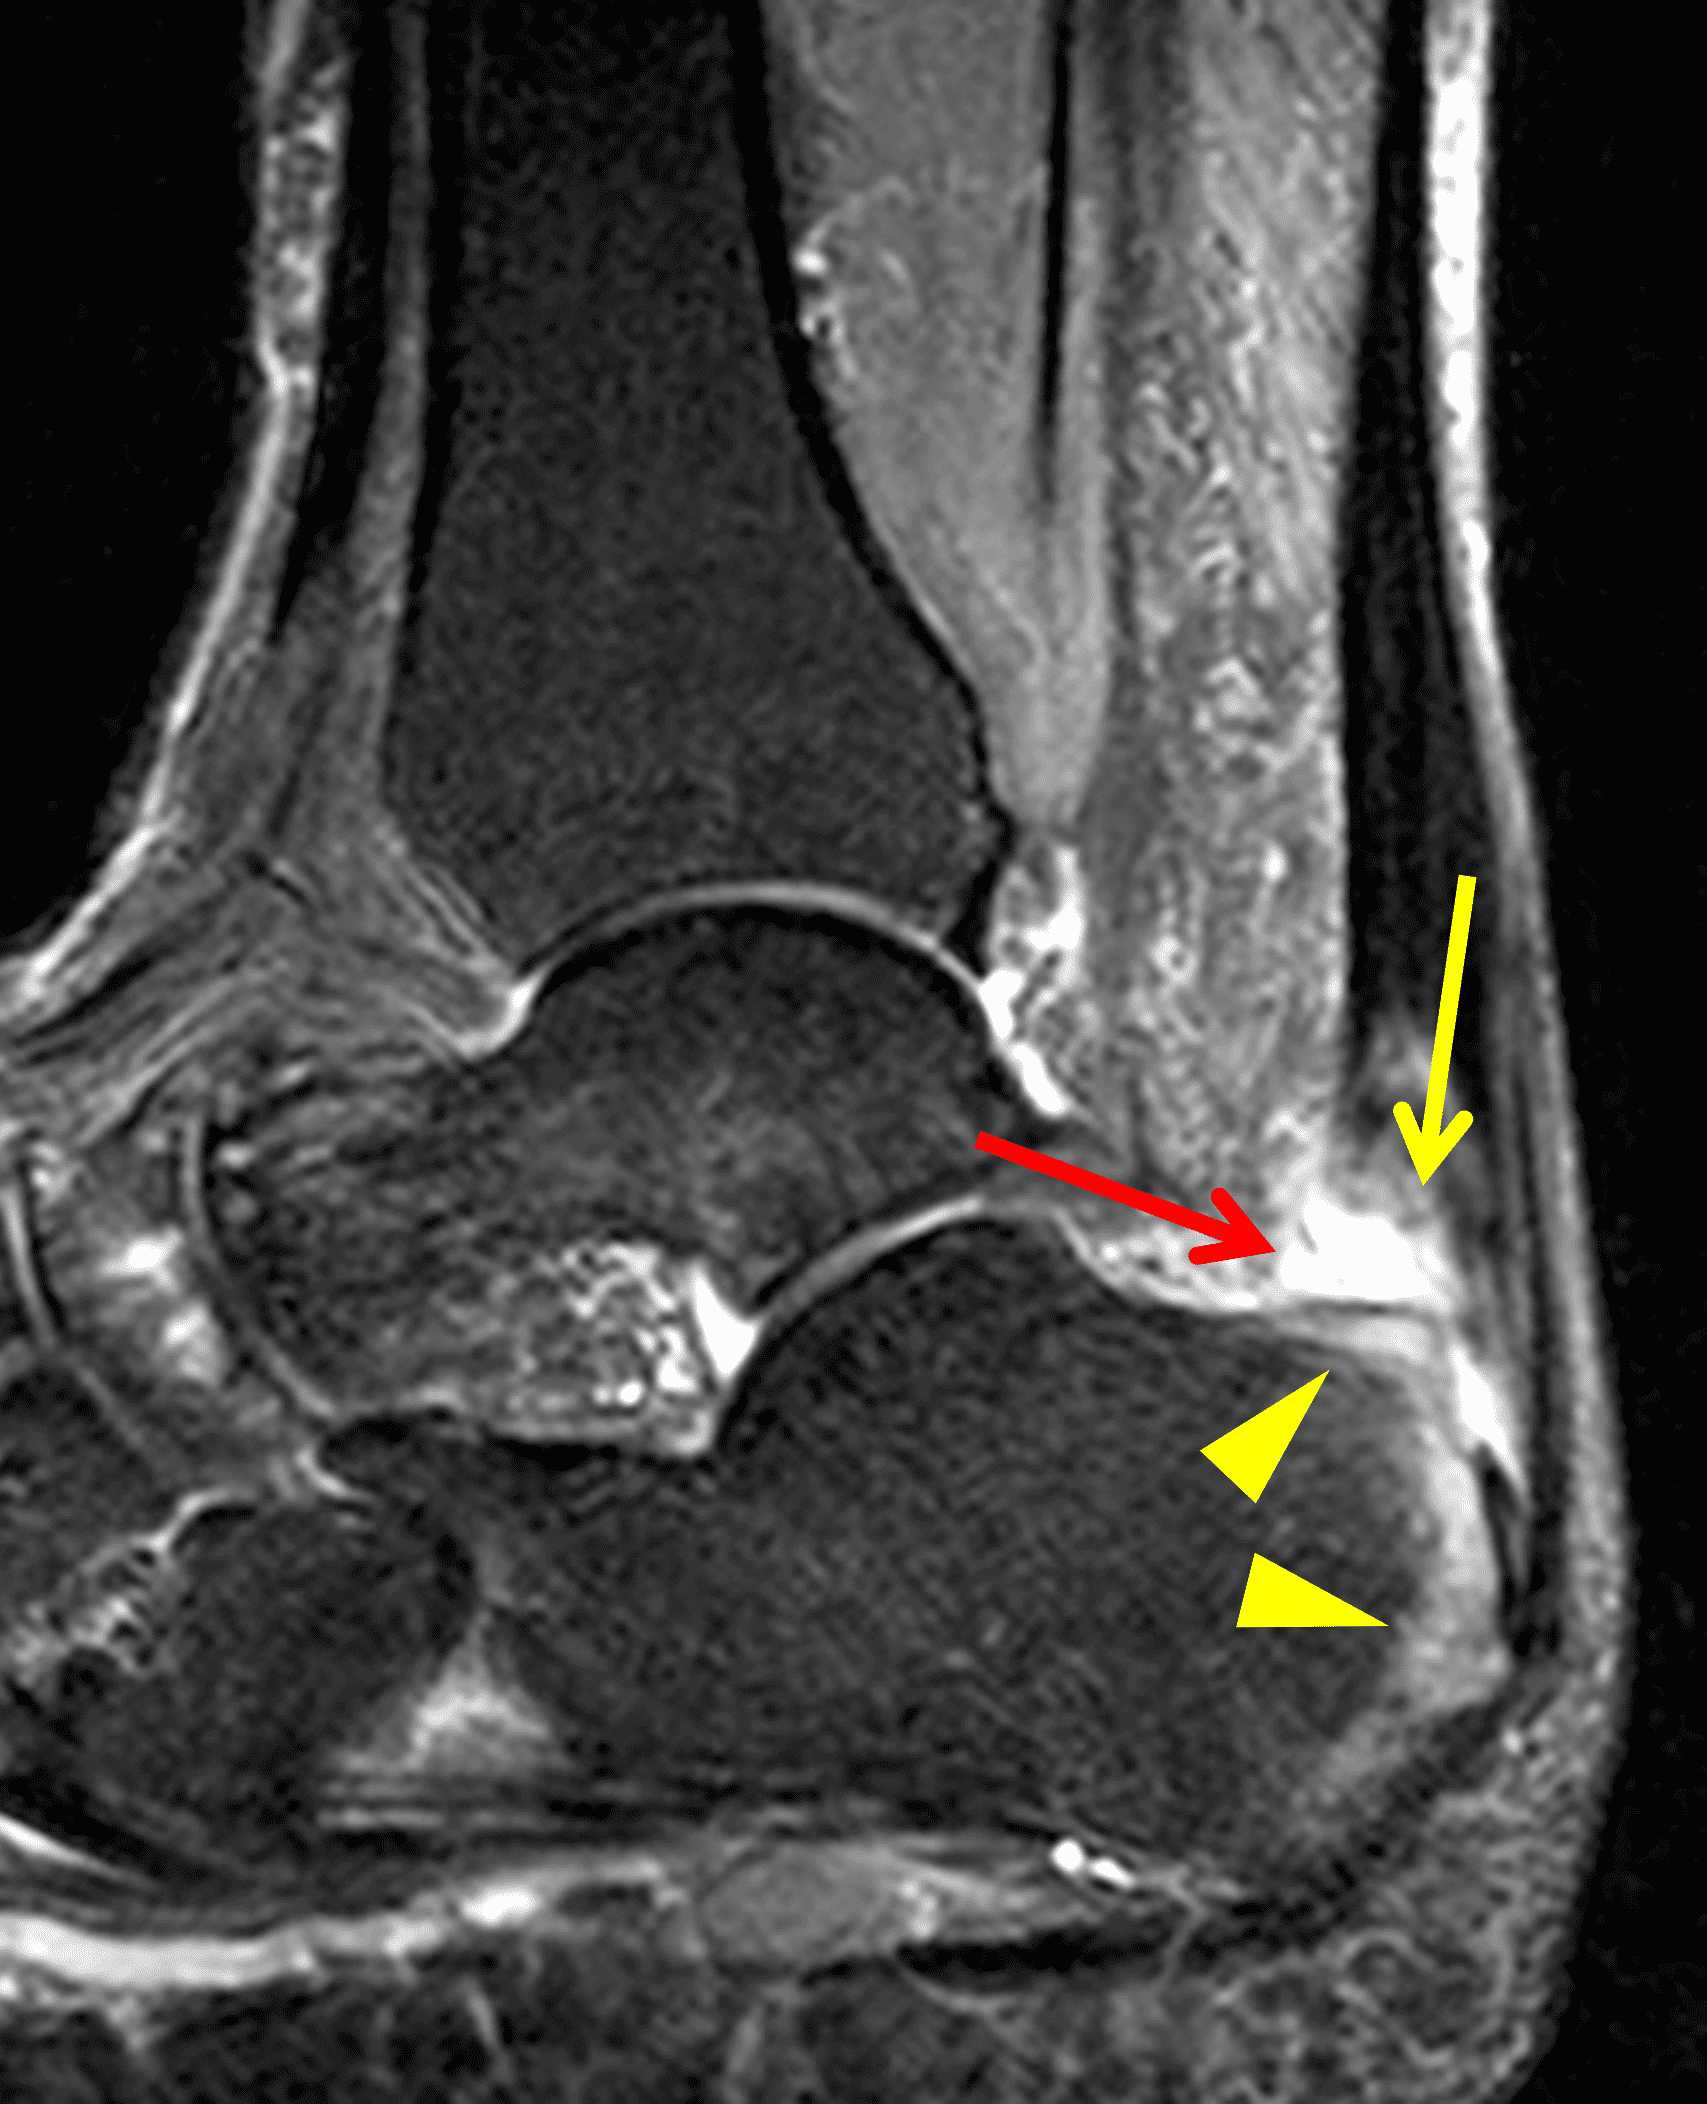

A 22 year-old male college football player presents with a “pop” and pain posterior to the right ankle during practice 1 week prior. He is unable to bear weight. Lateral radiograph (1A), sagittal fat-suppressed T2-weighted (1B), sagittal T1-weighted (1C), and transverse fat-suppressed T2-weighted images are provided. What is your diagnosis? What MRI findings affect clinical management decisions?

Figure 2: Complete Achilles tendon rupture. (2A) The lateral radiograph shows a thick and indistinct proximal Achilles tendon contour (arrows). (2B) A fat-suppressed T2-weighted image shows complete rupture of the tendon with a fluid-filled gap (yellow arrow) measuring 1.5 cm in length, located 10 cm cranial to the tendon insertion (blue arrow) and just distal to the edematous myotendinous junction (red arrow). The tear is superimposed on diffuse tendinosis. (2C) A sagittal T1-weighted image confirms the diffuse tendinosis. Fluid extends anteriorly into Kager’s fat pad (arrow) suggesting disruption of the anterior paratenon. (2D) A transverse fat-suppressed T2-weighted image through the proximal tendon shows no intact fibers (arrow), confirming the full-thickness rupture.

Acute, complete Achilles tendon rupture just distal to the myotendinous junction, superimposed on diffuse tendinosis.